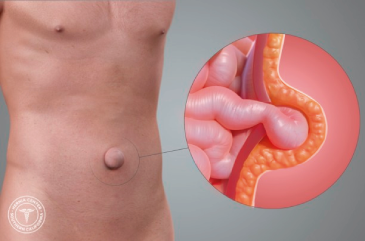

Hernias

Una hernia se presenta en alguna zona de debilidad de la pared abdominal, a través del cual protruye el contenido de la cavidad abdominal pudiendo ser un asa intestinal o tejido graso. Las hernias se manifiestan con dolor que se incrementa con el esfuerzo o movilización y zonas con aumentos de volumen cuyo contenido puede regresar al interior de la cavidad, requiriendo de manejo quirúrgico lo antes posible, ya que puede complicarse con la imposibilidad de retornar el contenido de la hernia hacia el interior sufriendo lesión de los órganos por falta de irrigación y por lo tanto que se requiera de cirugía de Urgencia. Las hernias se pueden presentar a diferentes niveles de la cavidad abdominal o pueden ser secundarias a procedimientos quirúrgicos previos, por lo que realizamos procedimientos quirúrgicos para la atención de:

- Hernias Umbilicales

- Hernias Inguinales

- Hernias Femorales

- Hernias Ventrales

- Hernias Incisionales

- Hernias de Pared Abdominal

Realizamos diferentes abordajes y técnicas para la reparación de los defectos herniarios llevando a cabo cirugía abierta o cirugía laparoscópica dependiendo de la valoración de cada caso, además de llevar a cabo la colocación de mallas para evitar la recurrencia. Además contamos con experiencia en el manejo de hernias ventrales grandes, en las que utilizamos diferentes métodos, toxina botulínica y diferentes mallas para lograr el cierre de la pared abdominal.

Hernia Umbilical